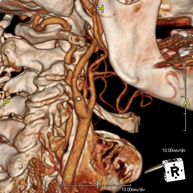

Prova diagnòstica no invasiva que consisteix en l'estudi de l'artèria aorta abdominal a través de l'obtenció d'imatges d'alta definició anatòmica mitjançant l'ús d'un equip de TC (Tomografia Computeritzada) i de contrast iodat. La qualitat de les imatges permet realitzar reconstruccions en 2D i 3D gràcies a estacions de treball especialitzades en l'estudi arterial. Està indicat en aquells pacients amb malaltia vascular (arteriosclerosi), en aneurismes d'aorta, en pacients amb dolor abdominal de possible origen vascular, en estudis prequirúrgics de lesions adjacents a l'aorta abdominal com a "mapa" vascular. La informació obtinguda de manera no invasiva és indispensable per als pacients que requereixen tractament percutani o quirúrgic. En aquells pacients que només requereixen seguiment de les lesions vasculars, aquesta tècnica és la tècnica no invasiva d'elecció juntament amb l'angio-RM. - Angio-TC Artèries renals

Prova diagnòstica no invasiva que consisteix en l'estudi de l'artèria aorta abdominal amb l'obtenció d'imatges d'alta definició anatòmica mitjançant l'ús d'un equip de TC (Tomografia Computaritzada) i contrast iodat. La qualitat de les imatges permet realitzar reconstruccions en 2D i 3D gràcies a estacions de treball especialitzades en l'estudi arterial. Està indicat en aquells pacients que pateixen malaltia vascular (arteriosclerosi), aneurismes d'aorta, en pacient amb dolor abdominal d'un possible origen vascular, en estudis prequirúrgics de lesions adjacents a l'aorta abdominal com el "mapa" vascular, etc. La informació obtinguda de forma no invasiva és indispensable per als pacients que requereixen tractament percutani o quirúrgic. En aquells pacients que només requereixen un seguiment de les lesions vasculars, aquesta tècnica és la tècnica no invasiva d'elecció juntament amb l'angio RM. - Angio TC d'artèries renals